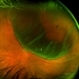

- https://imagebank.asrs.org/file/15894/retinal-detachment-right-eye-optomap See the previous submission above using an Optos TX 2000. Now, 12 years after his RD OD surgery, he remains attached. Comparatively one of the most amazing cases I've been privileged to be part of. This RD Repair from 2014 still going strong! Camera: Optos California